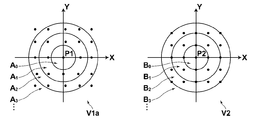

- the division condition in the first embodiment is that the deformed first image is divided into a plurality of first divided images according to the distance from the predetermined position, and the second image is determined from the position corresponding to the predetermined position of the first image. Division into a plurality of second divided images corresponding to the first divided image based on the distance. Then, the evaluation function S ( ⁇ ) in the second embodiment is obtained for each of the pair of divided images including the first divided image and the second divided image corresponding to the first divided image according to the division condition. A divided image similarity representing the similarity of distribution of pixel values is defined, and the similarity between the image V1a obtained by modifying the first image and the second image V2 is evaluated based on each divided image similarity.

- the image deformation amount estimation unit 12 sets a second divided image obtained by dividing the second image in accordance with a preset division condition. Specifically, the reference point P2 of the second image V2 is specified based on the input of the user input device, and the distance between the reference point P2 and each control point X in the second image is calculated. Then, depending on the distance from the reference point P2, the range of a predetermined distance d 0, d 1, d 2 , ..., each d k, sets the second image V2 as a plurality of second divided images, the divided Information for specifying the image is stored in the memory (S02).

- the first image V1a and the second image V2 deformed according to the angle instead of the distance may be divided.

- a value obtained by replacing the distance d in the expression (3) with the angle ⁇ can be used as the evaluation function.

- the first image and the second image which are deformed according to one spatial parameter called the angle from the reference graphic, are divided, and according to the angle from the reference graphic (reference x-axis).

- Te range theta 0 predetermined angular, theta 1, theta 2, ..., every theta k, if the information specifying the corresponding respective first image and the second image stored in the memory, modified